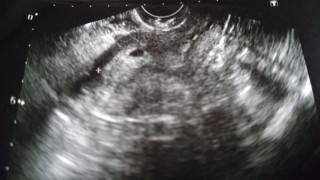

5週5日まで病院に行きました。 胎嚢しか見えなかったうえ、胎嚢が細長いので心配していましたが、この日から2週間後の7週5日に心拍まで確認でき、この時は胎嚢も丸くなっていました。